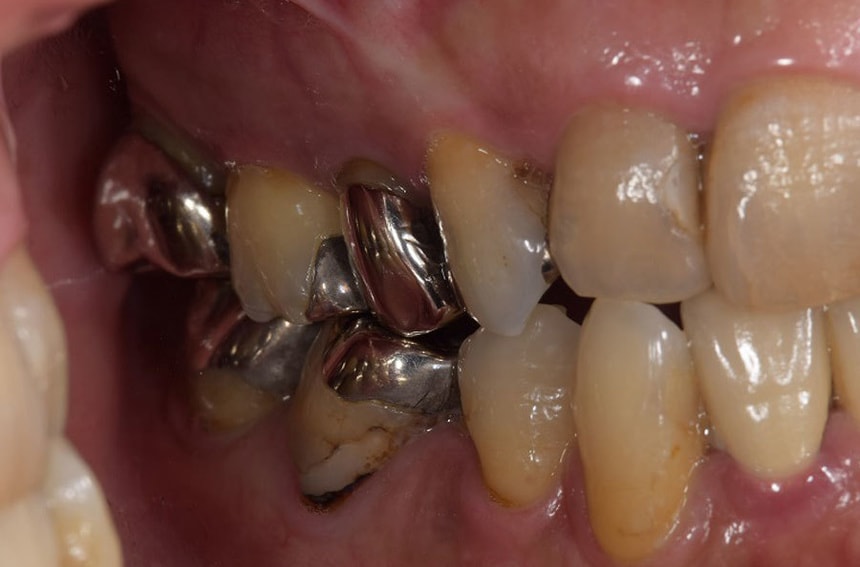

右奥歯の治療前後

治療前のかみ合わせのままで治療しても長持ちしないこと、本来のかみ合わせから崩れてしまっていると判断し、お口の中を総合的に治療する治療方法を提案させていただき治療を行いました。

咬むと前歯が痛いと来院された患者さん。奥歯がないため、前歯に負担がかかり、下の歯がないまま放置していたため、上の歯が下に下がってしまうなど様々な問題をお口の中に抱えていました。

残すことが出来ない歯の抜歯などを行うと、すれ違い咬合という治療するには難しいかみ合わせであったことなど、仮の入れ歯などで咬合状態の経過観察などを行ったため治療期間は約2年ほどかかりました。

治療の内容にもよりますが、しっかり診断し治療を行っていくとどうしても治療期間がかかってしまいます。患者さんにはその点ご理解いただけると幸いです。